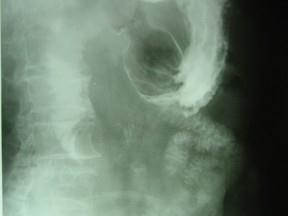

问题 女 ,80岁 ,右上腹疼痛反复发作 6个月,加重 2天 ,曾有胆囊炎及胆结石病史,影像检查如图,应诊断为 ( )

选项 A、十二指肠间质瘤 B、十二指肠腺瘤 C、十二指肠巨大胆结石(胆囊十二指肠瘘) D、十二指肠蛔虫 E、十二指肠息肉

答案 C